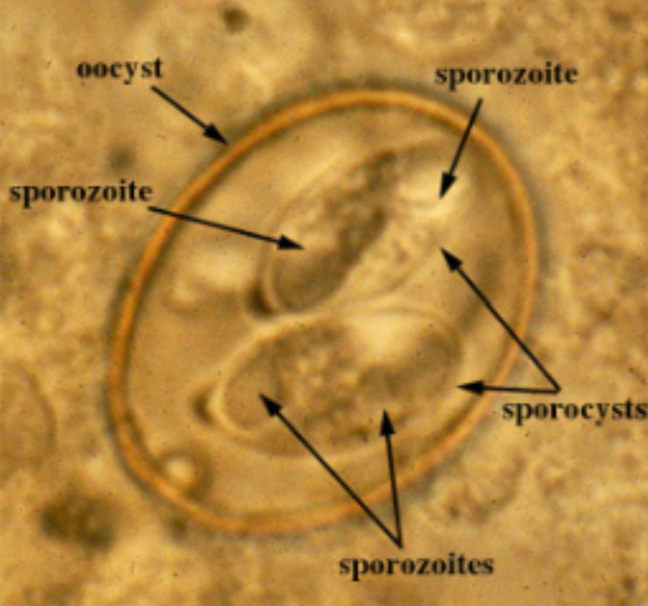

Toxoplasma gondii Oocysts

Isospora belli Oocyst